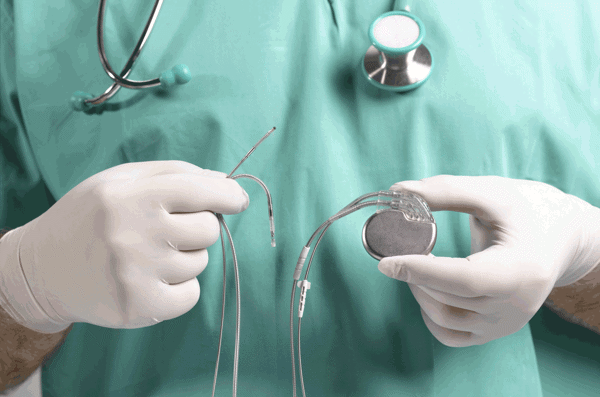

液态硅橡胶LSR

液体硅橡胶是一种高纯度的双组分铂固化硅胶,是生产对强度、耐性和质量要求较高的技术部件的理想配方。液体硅橡胶是一种粘稠但可泵送的材料,主要通过液体注射成型(LIM)进行加工